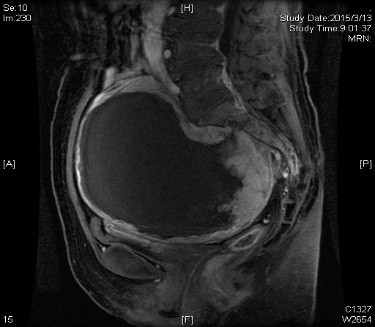

经进一步术前检查发现,尚女士肿瘤位于盆腔内,大小约25*20*20cm,瘤蒂位于右侧骶1-2骶前孔,部分实性成分位于右半骶骨内,在骶孔中塑形生长,手术暴露困难;瘤周异常血管网丰富,与髂总及髂内血管及骶前静脉丛毗邻,术中极易发生难以控制的大出血。不仅如此,肿瘤邻近膀胱、子宫及直肠,周围脏器易受损伤;右侧输尿管下段受到肿瘤压迫,右肾积水征象明显。为确保手术的安全性,术前神经外科、普外科、泌尿外科、血管外科等多名专家对病例进行了多学科讨论。血管外科吴巍巍主任指出,为预防术中发生大出血可考虑先予以腹主动脉球囊阻断,多次与患者及家属沟通,遗憾的是患者及家属拒绝预先行阻断手术,术中出血的风险再次增加。